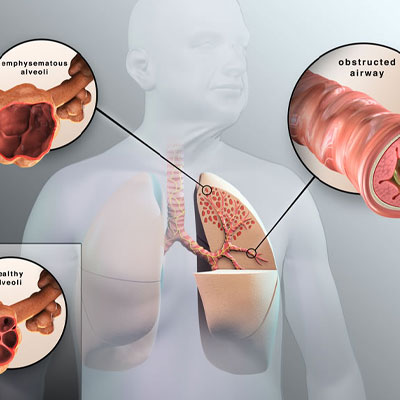

Consultation of ILD from interventional pulmonology doctors in Hyderabad at lung hospitals depends on the type of diagnosing and severity. So, its consultation generally includes, relieving symptoms, improving quality of life, and slowing disease progression.

Whereas, if ILD is developed in pulmonary hypertension then doctors at chest medicine hospitals in Hyderabad consult treatment from supportive therapy or PH-specific therapy

Is there any treatment for severe Asthma patients?

Bronchial thermoplasty, a non invasive interventional procedure which can help calm the muscles of the lungs.